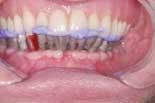

On the day of surgery, the remaining lower teeth are extracted (figure 3) and alveoplasty performed. Branemark Mk III TiU implants were placed in the 37, 36, 34, 44, 46, 47, and 31 sites. Branemark RS TiU implants were placed in the 43 and 33 sites. All implants were torqued to 45 Ncm. Multi-unit abutments were placed on the implants and torqued to 35 Ncm (figure 4). Bioss 1:1 autogenous grafting was done in the anterior region (figure 5) and the sites closed with chromic gut sutures. The maxillary CUD was inserted and the CLD was modified and relined with tissue conditioner.